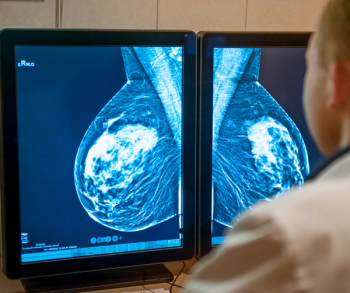

In a recent video interview, Kathy Schilling, M.D., discussed findings from a study of ProFound AI, an adjunctive artificial intelligence (AI) software for digital breast tomosynthesis (DBT), that demonstrated a 23 percent increase in breast cancer detection in comparison to DBT alone.